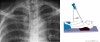

3. Acromioclavicular joint

1) AP view(Zanca view)

Demonstrates: AC joint and distal clavicle

Helpful for: Acromioclavicular Arthritis, Acromioclavicular Joint Separations, Distal Clavicle Osteolysis, Distal Clavicle Fracture

AC joint spurring and cystic changes indicates Acromioclavicular Arthritis.

Distal clavicle elevation indicates Acromioclavicular Joint Separations.

Position: Erected with cassette behind shoulder. Beam:Xray beam aimed at the AC joint in 10° to 15° cephalic tilt. Xray penetration should be 1/2 normal to avoid overpenetration of AC joint.

2) Weighted(stress) view